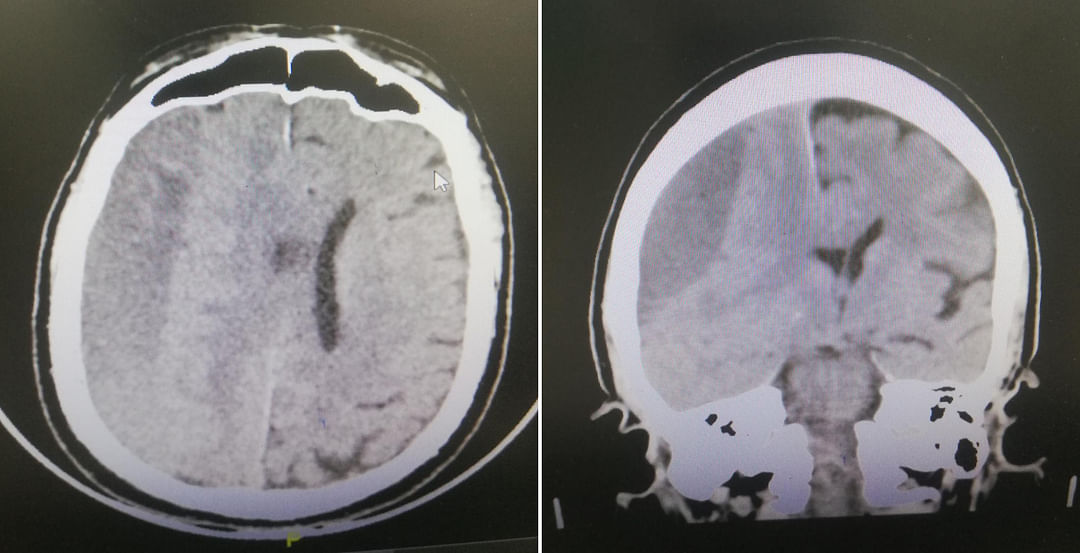

وقال المتحدث الرسمي لصحة الطائف وليد الثقفي؛ إن الفريق الطبي بالمجمع قرر على الفور عمل أشعة مقطعية للمخ، وتبيّن فيها وجود تجمع دموي كبير (نحو 138 سم مكعب) تحت الأم الجافية في المخ، أدى إلى بداية فتق مميت بالمخ.

وعليه فقد قرر الفريق إجراء جراحة عاجلة استغرقت أكثر من ساعتين تم خلالها تفريغ التجمع الدموي مع فتح للتكيسات تحت الأم الجافية والسيطرة على النزيف ما أدى إلى رجوع تدريجي للمخ وإيقاف اكتمال الفتق المميت.